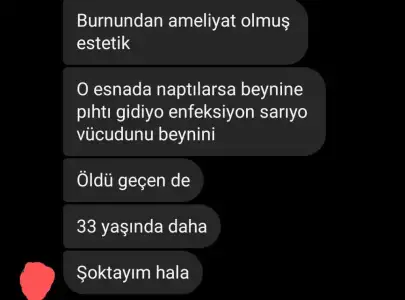

Bu arada doktorunuzu iyi araştırın derim.Bugün bir arkadaşımla konuşurken özel bir klinikte burun estetiğinden sonra beyne pıhtı atıp enfeksiyon sonucu vefat eden 33 yaşındaki gencecik bir yakınının vefat ettiğinden bahsetti.

Aldığınız basit bir karar değil,bir anlık kararla olmamalı üzerine iyice düşünün bence.

Bu arada doktorunuzu iyi araştırın derim.Bugün bir arkadaşımla konuşurken özel bir klinikte burun estetiğinden sonra beyne pıhtı atıp enfeksiyon sonucu vefat eden 33 yaşındaki gencecik bir yakınının vefat ettiğinden bahsetti.

Aldığınız basit bir karar değil,bir anlık kararla olmamalı üzerine iyice düşünün bence.